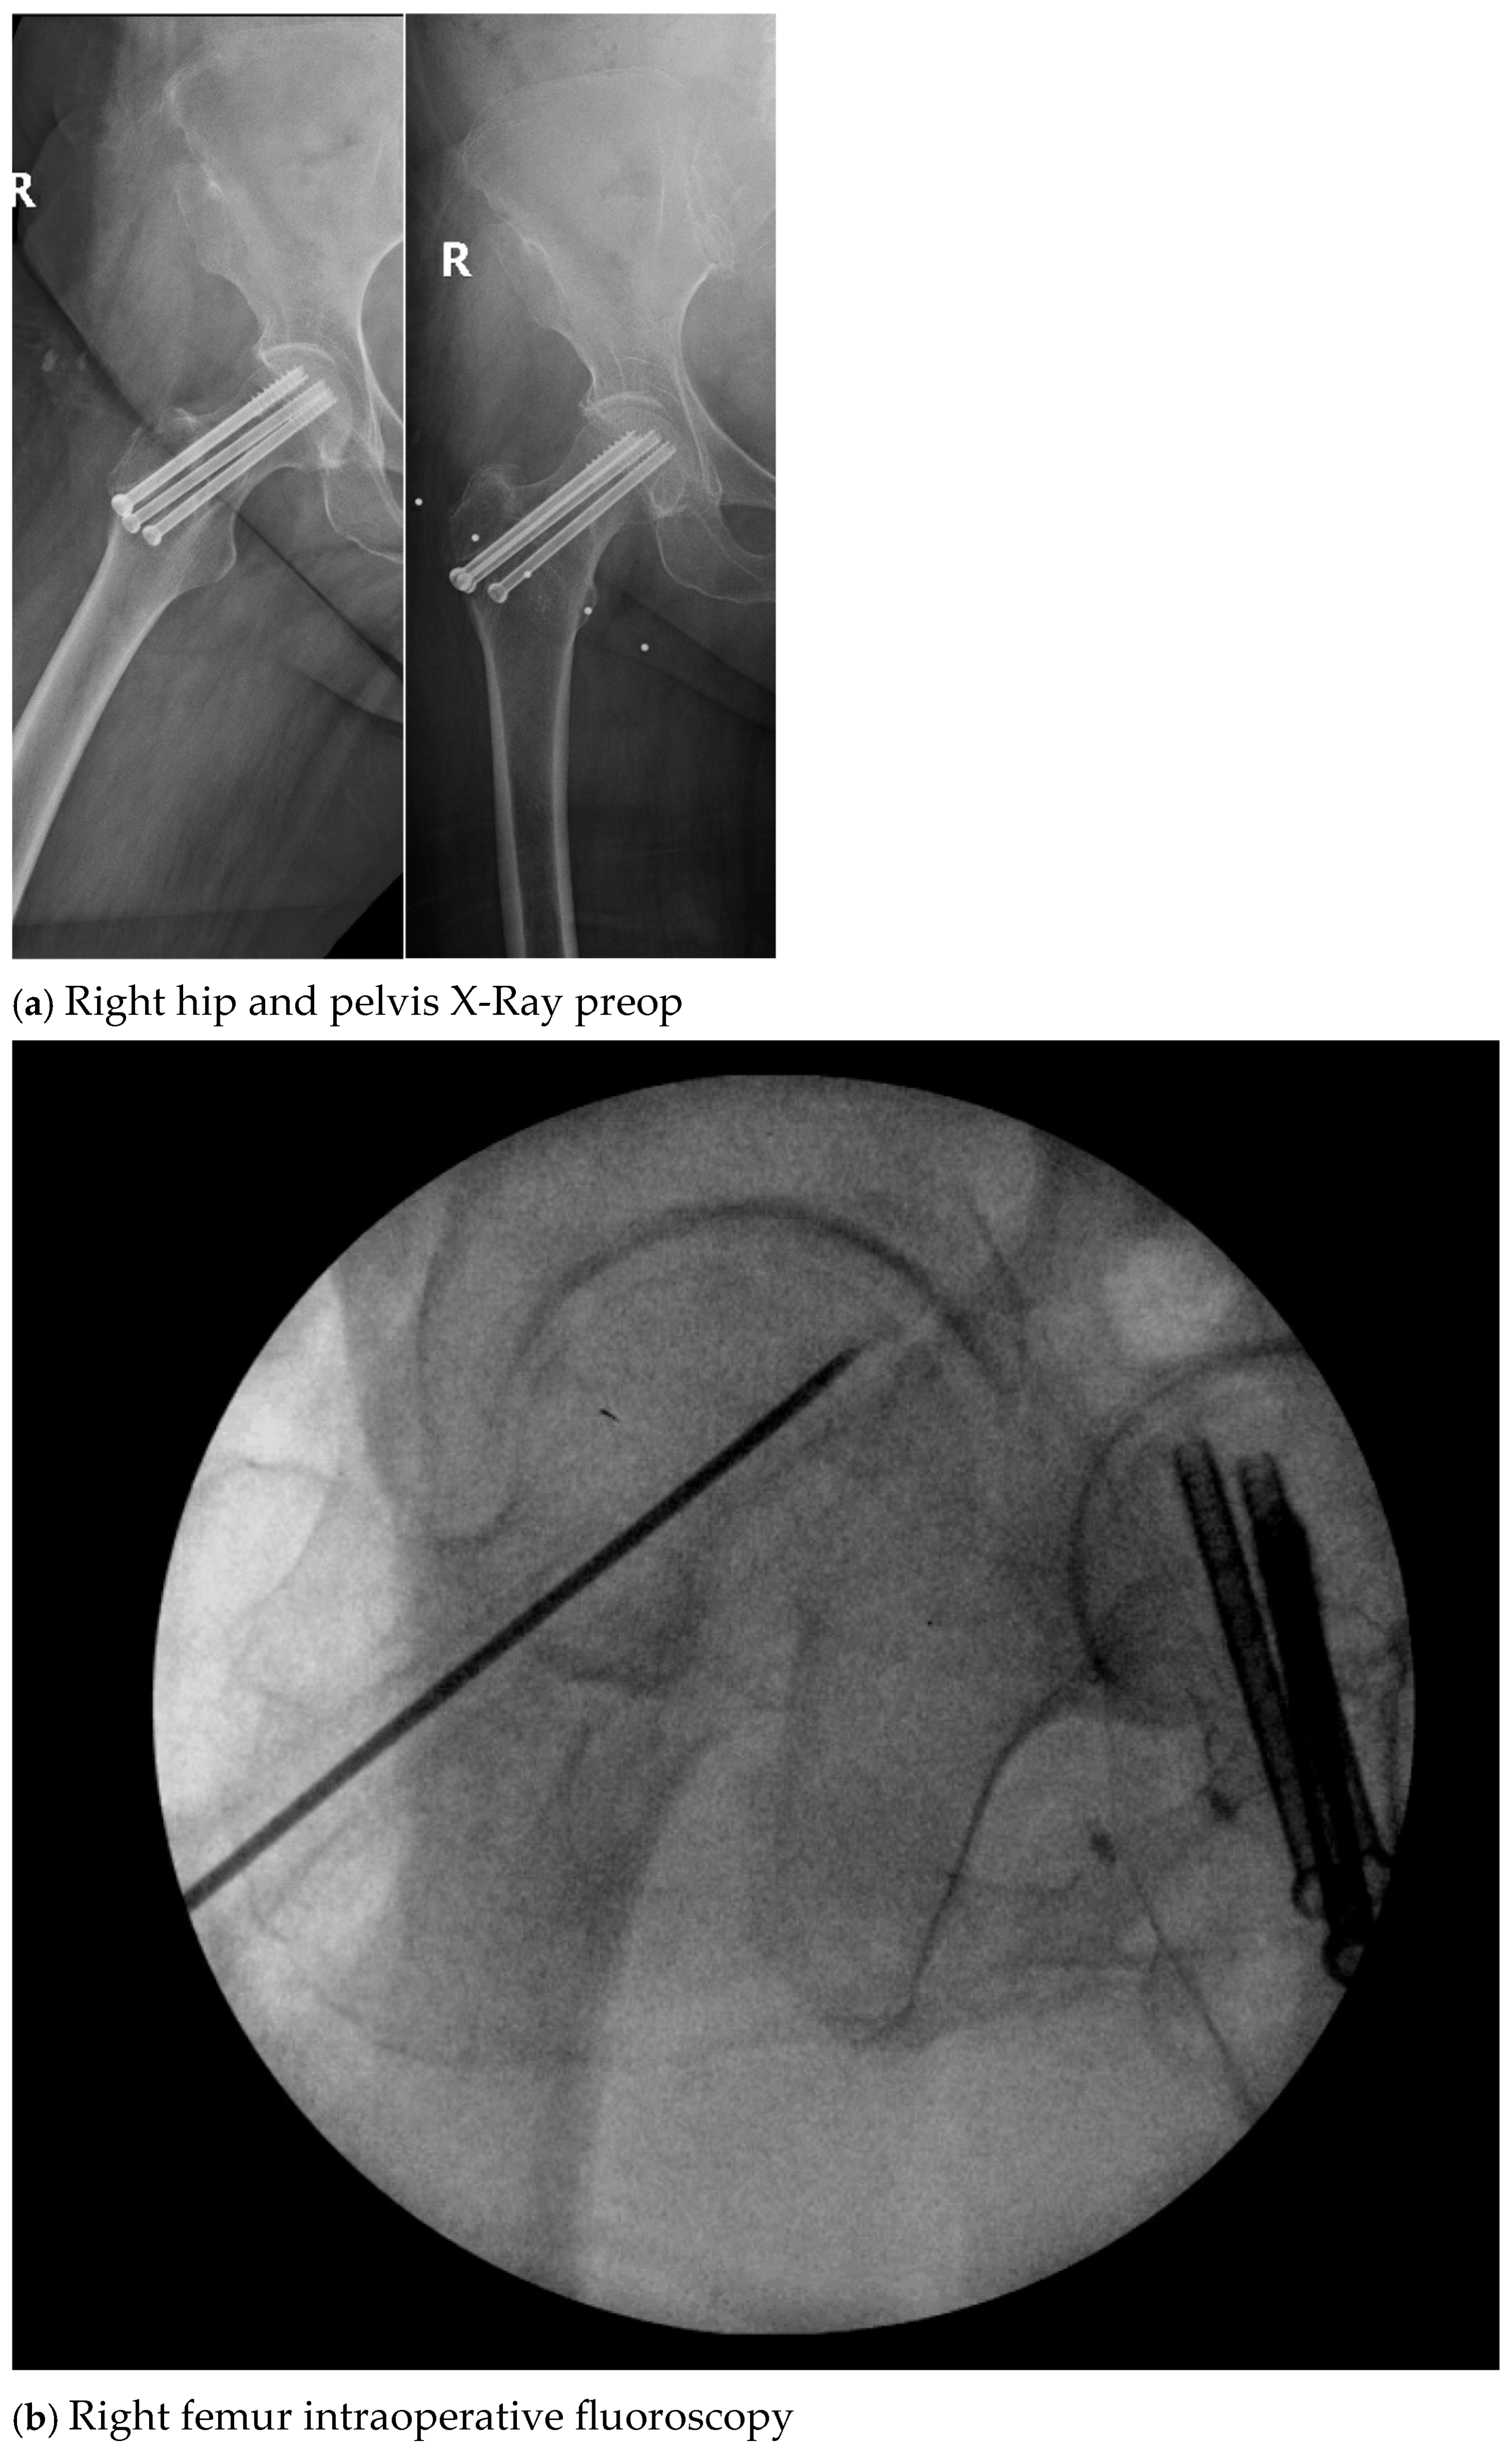

| 4. | 75 | F | Y | N | 20 | N | N | 17 | Right thigh and gluteal abscess with infected right femoral neck hardware and osteomyelitis |

| 4. | N | N | 14 | 4 | Y, clinical and lab | 107 | Negative |